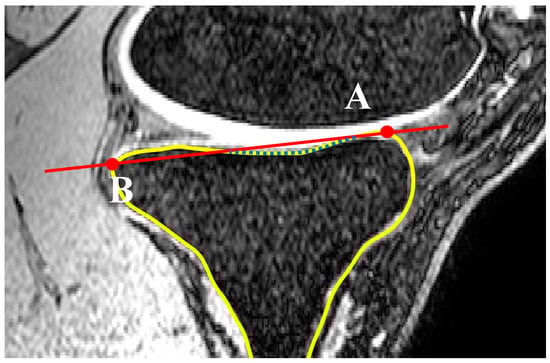

2.1. Medial and Lateral Tibial Slope Measurement Methodology